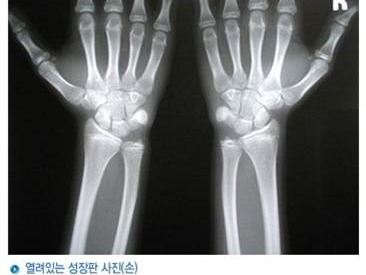

성장판이 열려 있어야 키가 큰다

열려있는 성장판 사진(손)

성장판이 닫히는 순서는 손가락 ,발가락->무릎->손목->척추 순입니다.

성장검사에서는 성장호르몬검사, 뼈나이, 성장판검사가 가능합니다.